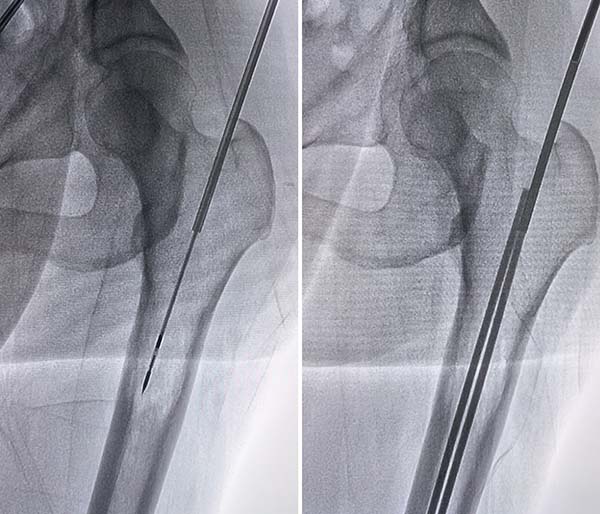

手术在DSA介入手术室顺利开展,由张开贤现场指导,于世平主任团队密切配合、协同发力。手术采用DSA实时影像精准定位病灶,分步有序开展诊疗操作:首先通过微波消融技术,利用高温精准灭活肿瘤细胞,有效控制肿瘤进展、缓解患者疼痛;随后在影像引导下精准实施经皮内克氏针固定术,为受损股骨提供稳固支撑,有效降低病理性骨折风险;最后行骨水泥成形术,将骨水泥精准注入病变骨骼区域,进一步加固骨骼强度、恢复骨骼稳定性。全程微创精准、出血少、创伤小,圆满达成手术目标,充分彰显了联合微创技术的临床优势。